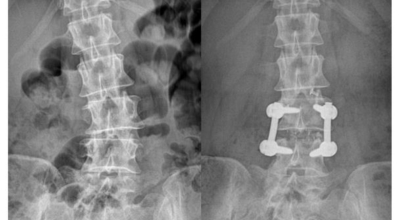

요추관 협착증은 척추 내 신경이 지나가는 통로가 좁아지는 현상으로 기인해서 신경이 눌리면서 이에 따른 여러가지 증상을 유발하는 질환을 의미해요.

허리 협착증은 척추관이 좁아지게 되면서 신경을 압박하게 되어 허리통증과 또한 다리에도 여러가지 증상을 일으키게 되는데, 발생 원인은 주로 노화로 인한 퇴행성 변화가 많았지만 요즈음는 옳지 않은 자세로 오랫동안 앉아있는 사람들이 많아지면서 생기는 경우도 많아졌으며, 선천적인 요인으로 나타나는 경우도 있답니다.